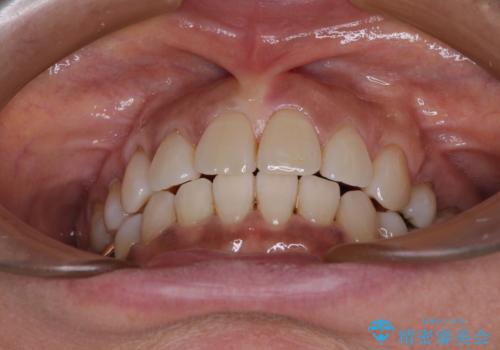

- 八重歯やクロスバイトを気にして来院された患者様です。

口元の突出感はありませんでしたが、デコボコが強く、非抜歯矯正とすると出っ歯仕上がりとなる可能性があったため、上下左右の第一小臼歯4本を抜歯し、ワイヤー装置にて矯正治療を行うこととしました。

抜歯矯正により口元が引っ込みすぎて、ほうれい線が顕著となるのではないかと心配しておりましたが、矯正後にほうれい線が気になることはなく、口元もすっきりとした感じになりました。